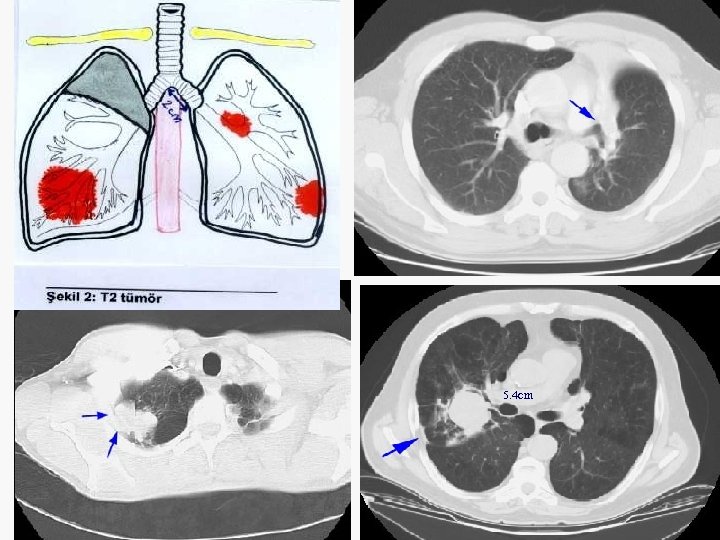

5. 4 cm

Evreleme EVRE 0 : Tis N 0 M 0 EVRE IA : T 1 N 0 M 0 EVRE IB : T 2 N 0 M 0 EVRE IIA : T 1 N 1 M 0 EVRE IIB : T 2 N 1 M 0 T 3 N 0 M 0 EVRE IIIA : T 1 -3 N 2 M 0 T 3 N 1 M 0 EVRE IIIB : T 4 N M 0 T N 3 M 0 EVRE IV : T N M 1